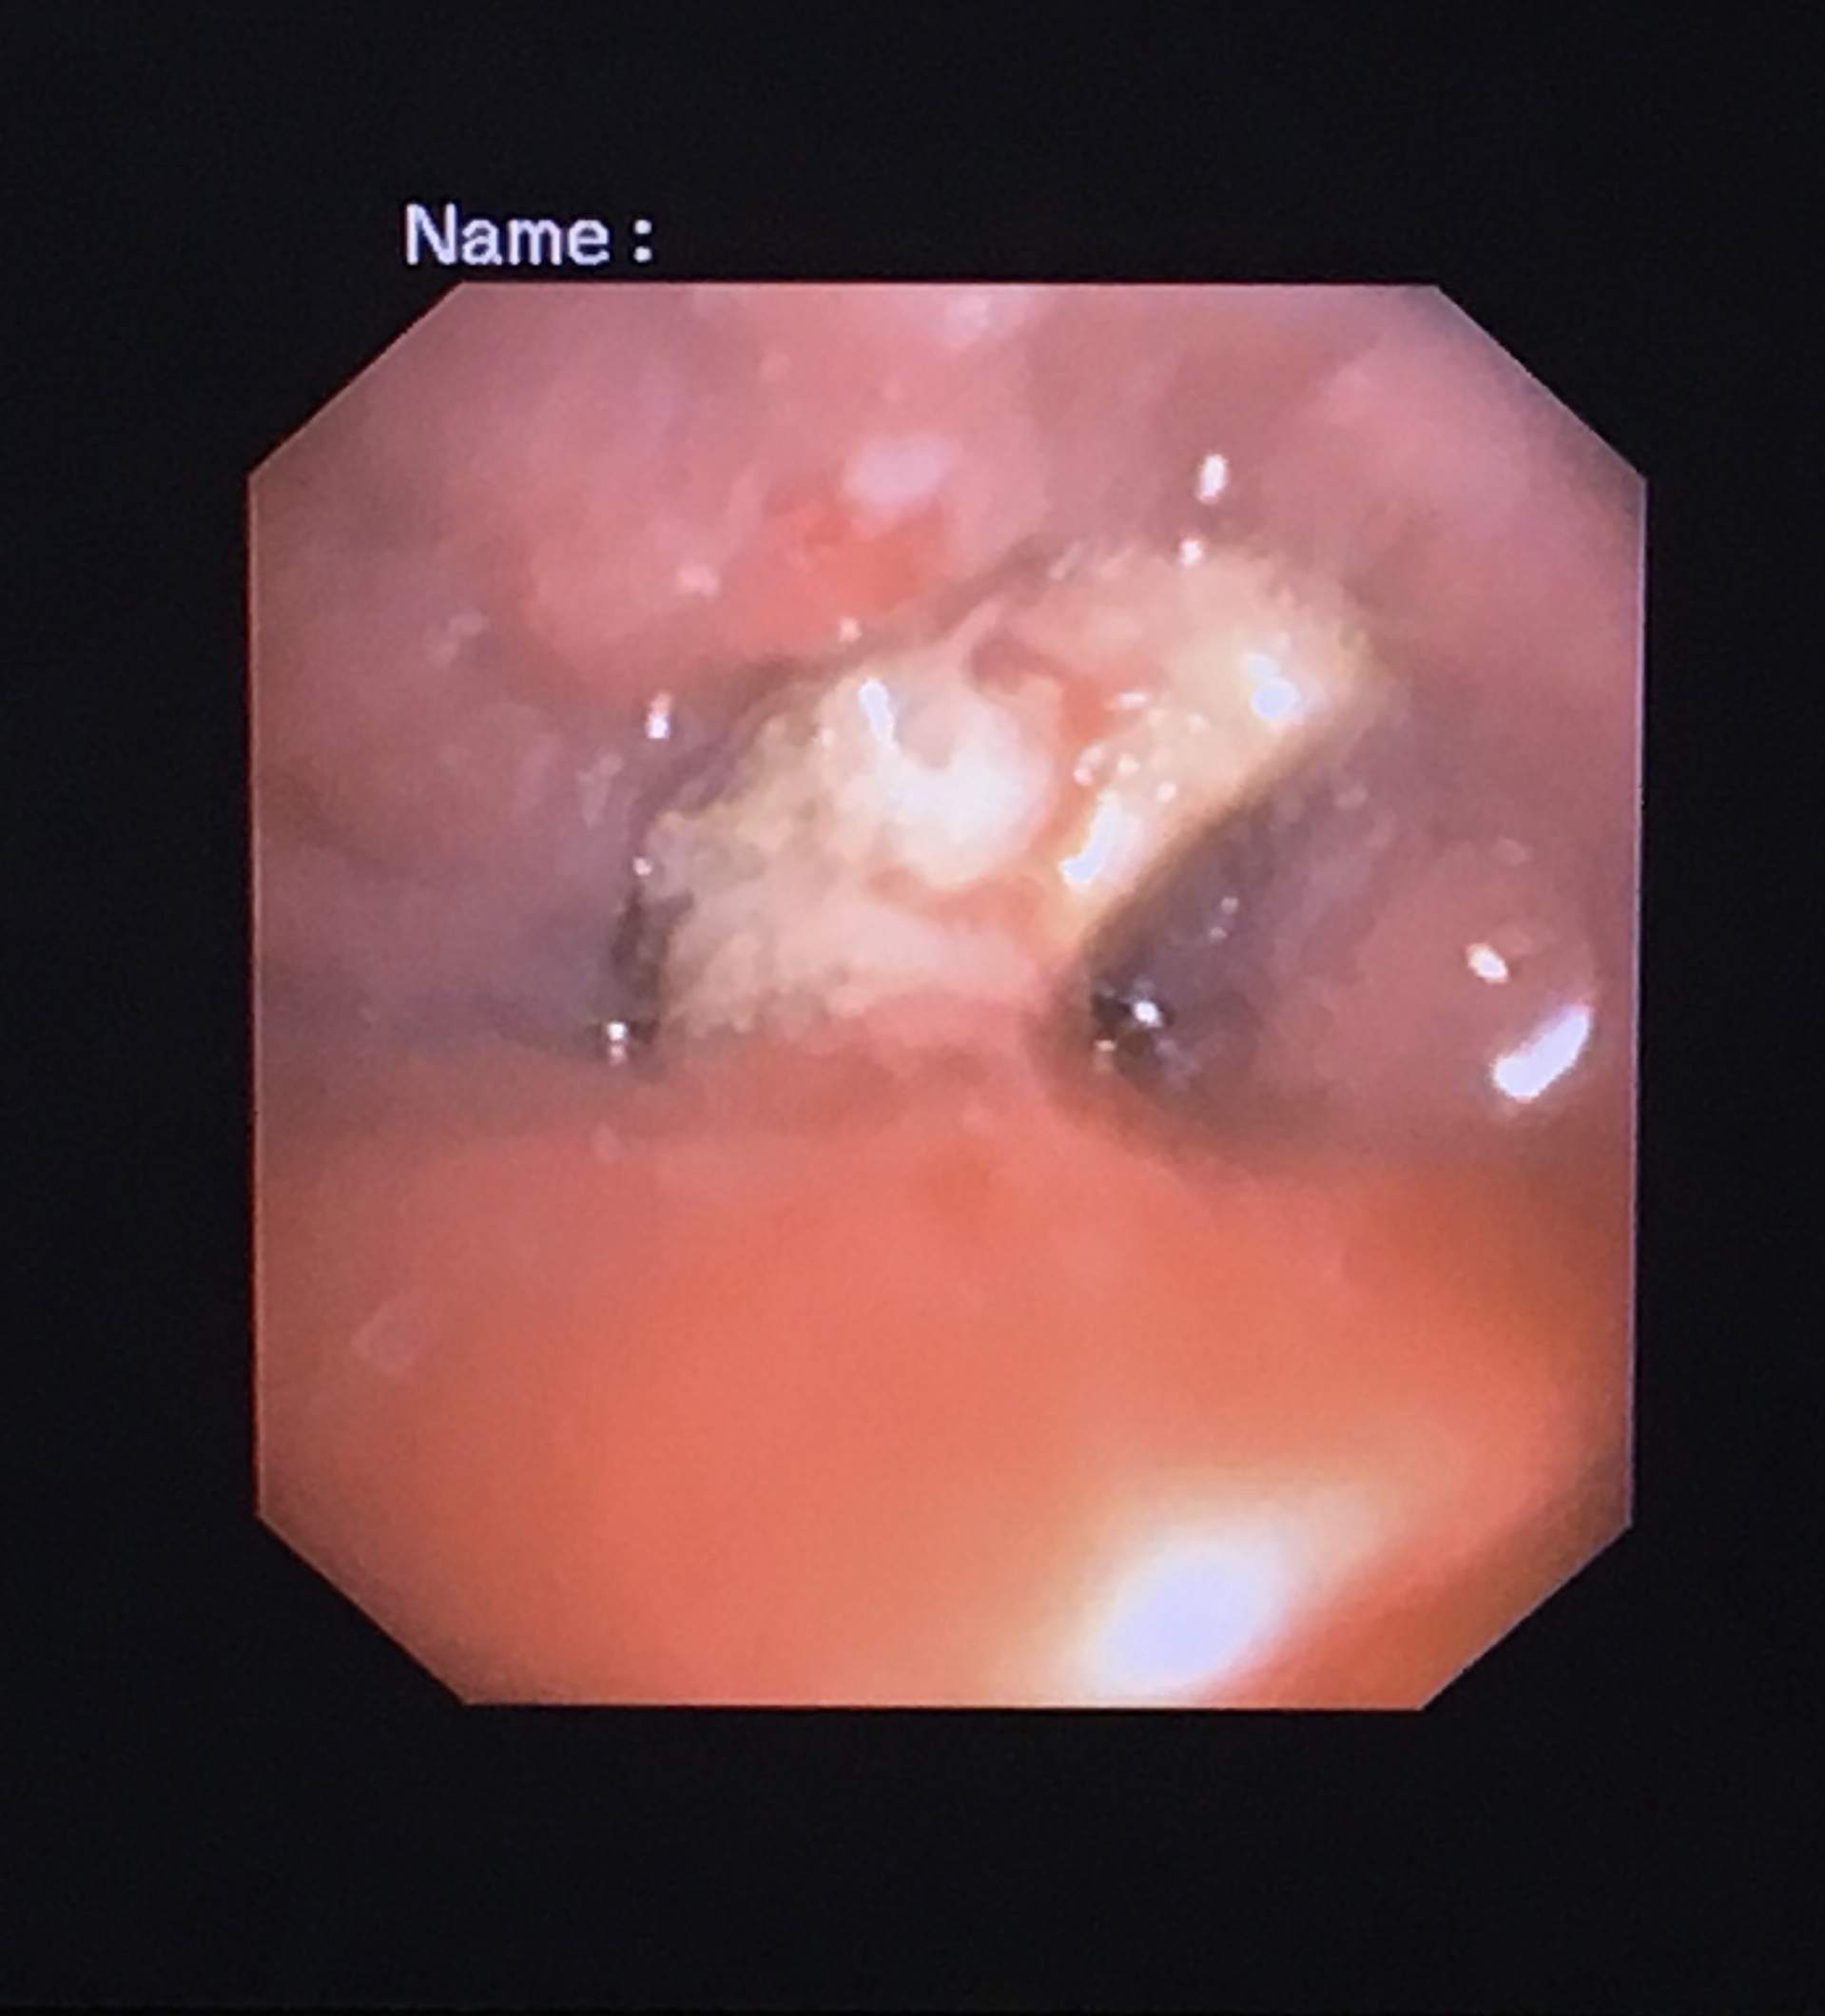

家住苍梧的陈阿姨今年71岁,反复咳嗽1年多无法康复,且近两个月病情明显加重,在外院住院治疗但收效甚微。经了解,陈阿姨来到我院就诊。入我院检查后,医生发现陈阿姨左下肺大片肺炎。此外,医生在肺部CT上还发现了不对劲的地方,于是采用行电子支气管镜检查,发现了导致陈阿姨肺炎反复治疗效果不佳的“元凶”——有异物嵌顿在支气管。

(患者陈阿姨支气管内异物堵塞)

由于这异物在气管内时间长,已引起支气管粘膜肉芽组织明显增生,并将异物紧紧包绕住,经多次纤支镜下钳取根本无法取出异物。